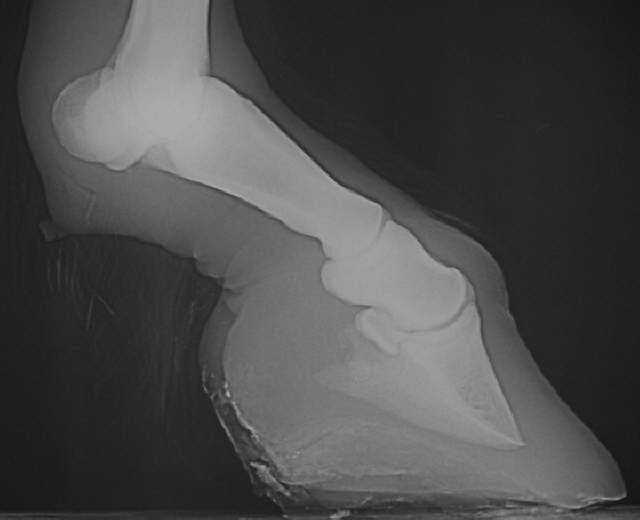

V-10.08.04

Bockhuf

Bockhuf wegen zu starken Zuges der tiefen Beugesehne mit Rotation des Hufbeines.